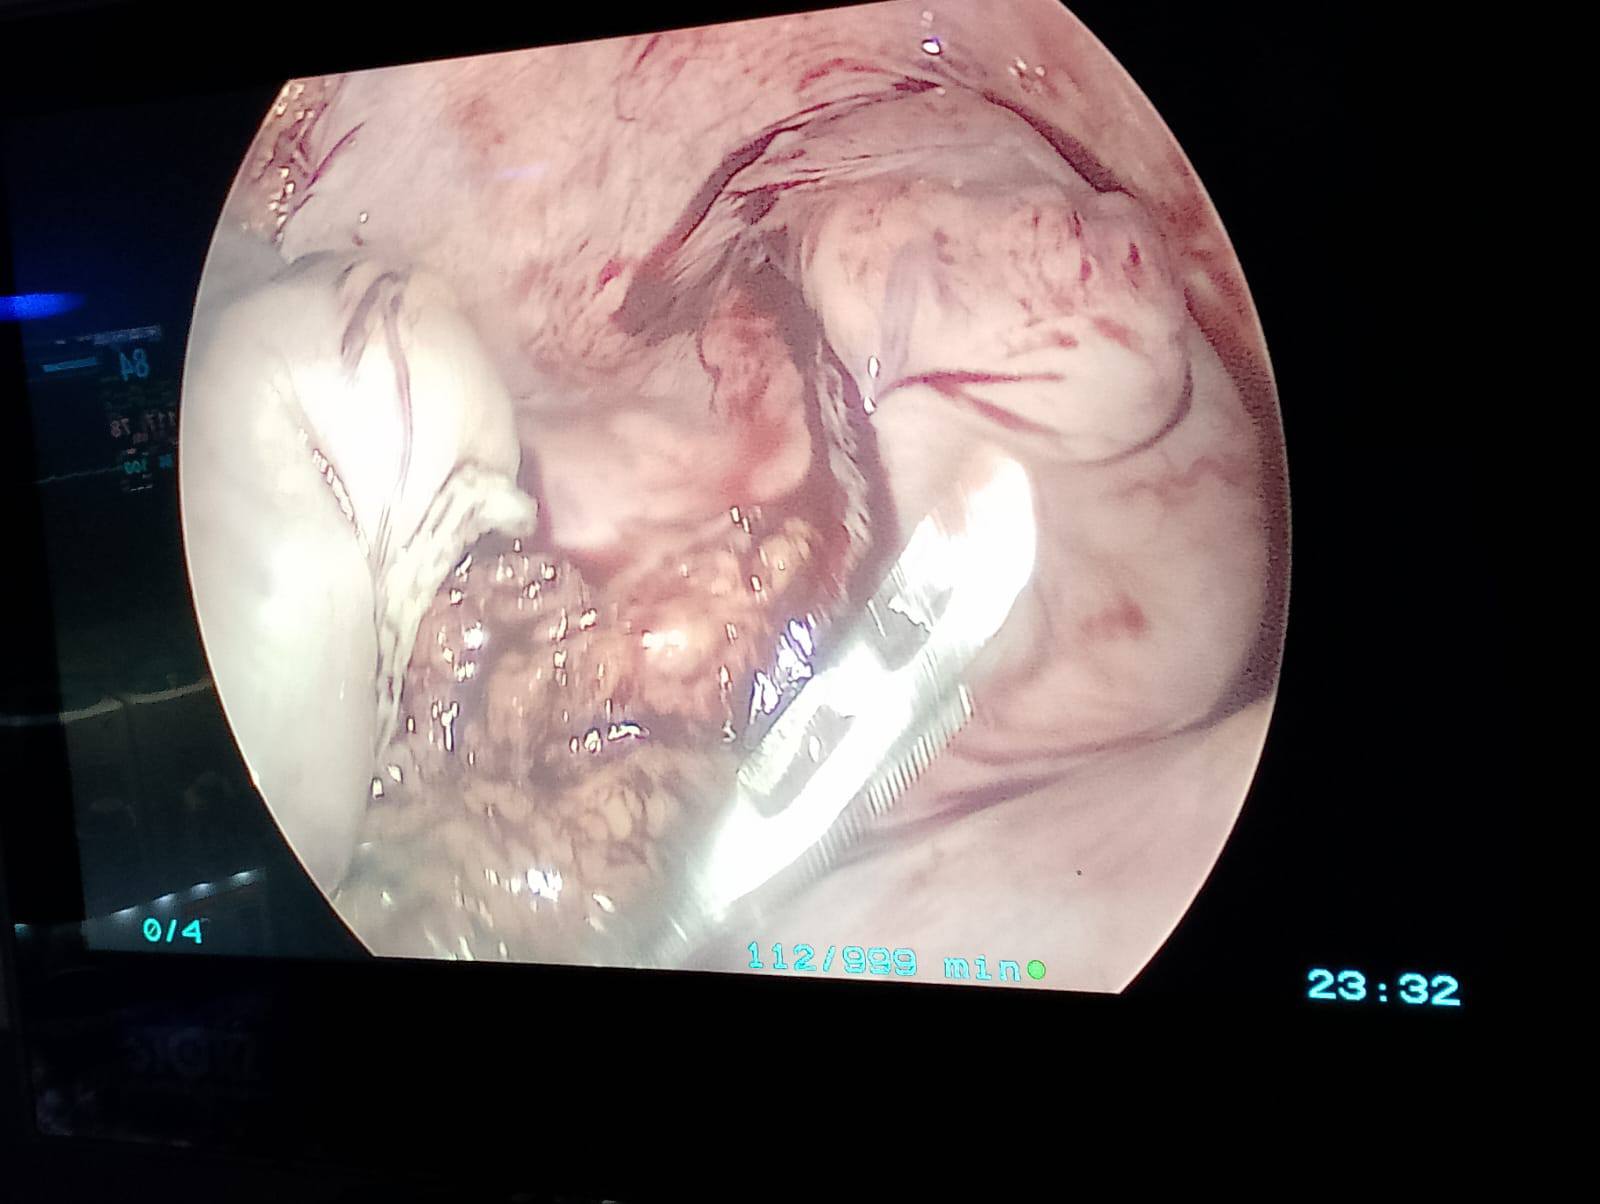

تم اليوم بحمد الله بالمستشفى الجامعى إجراء جراحة متقدمة لاستئصال كلى للقولون بالمنظار الجراحى مع عمل توصيل للأمعاء الدقيقة بالمستقيم لمريض يعاني من انعدام حركية القولون وتم خروج المريض بحالة جيدة بفضل الله.

A case of Laparoscopic total colectomy for a male patient with colonic inertia.